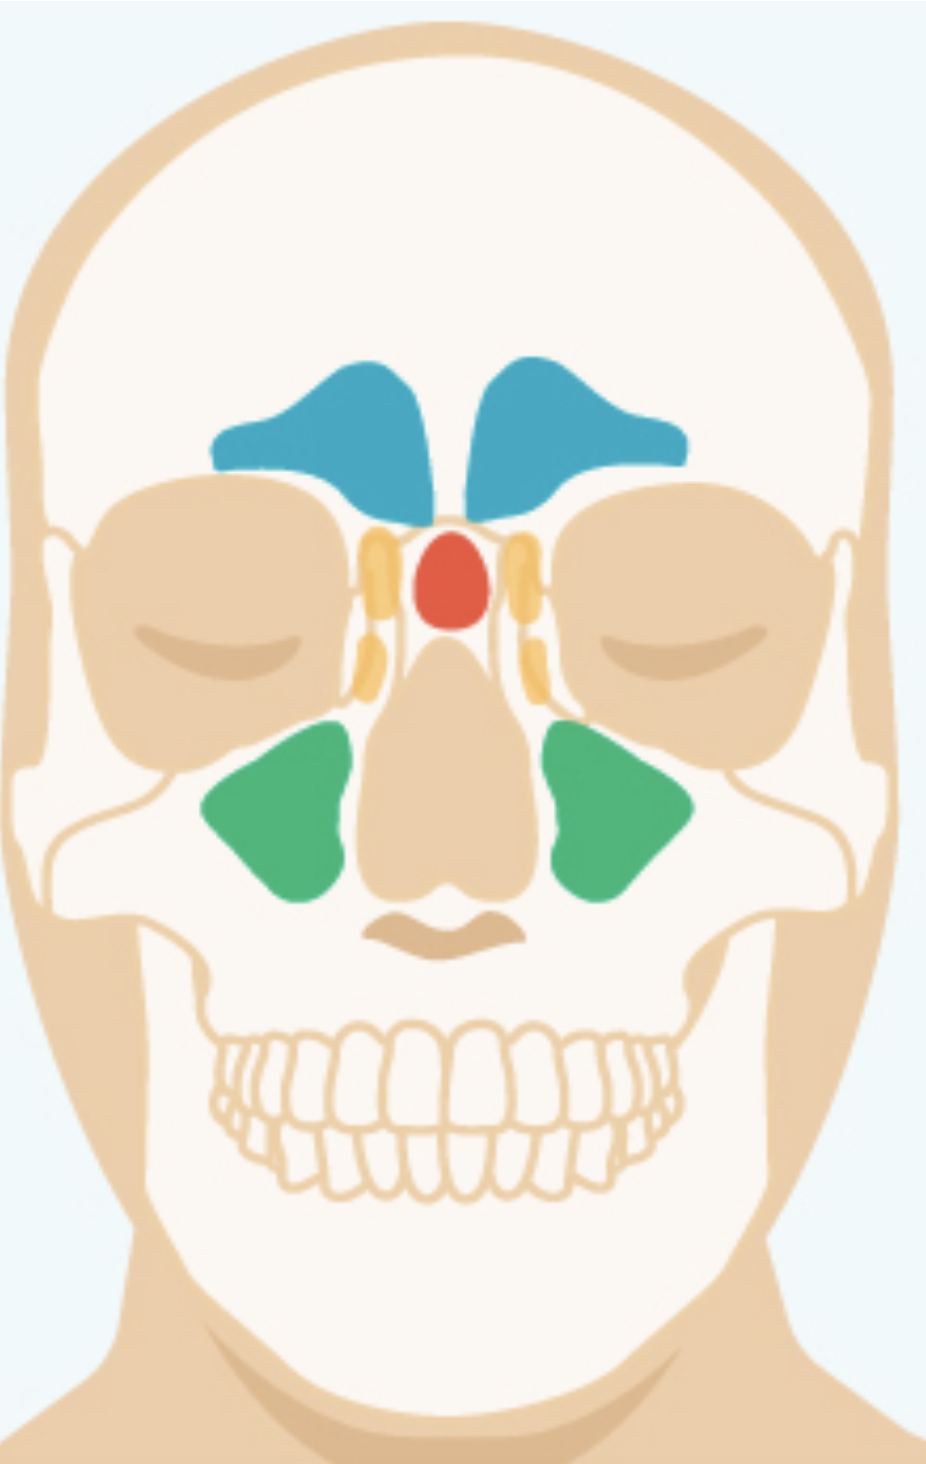

13

Q

Label the different Sinuses?

A

Red=Sphenoid Sinus

Green=Maxillary SInus

Yellow= Ethmoid Sinus

Blue= Frontal Sinus

14

Label the different sinuses

Blue=Frontal Sinus

yellow=Ethmoid Sinus